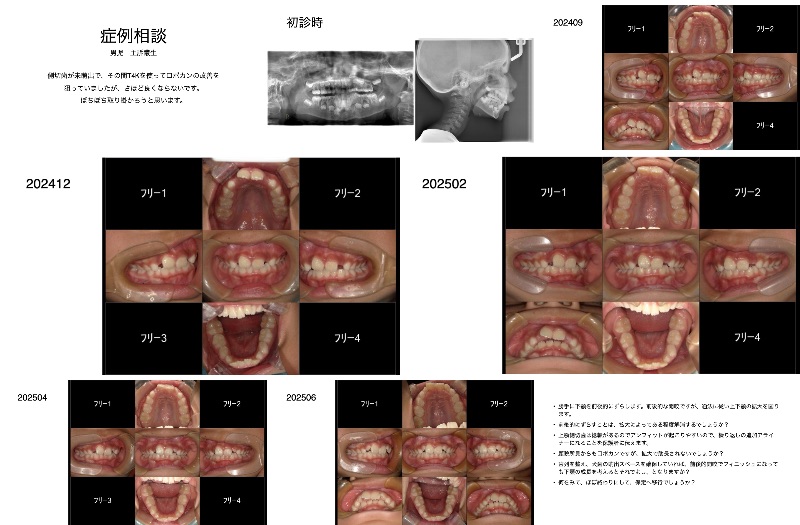

症例相談会で、これから取り組む、T4kを使っている症例です。

小学生なのですが、Teenで取り組んだ方がよいですか?5年なので18歳まで見ていくにはちょっと足りません。

がKinderでは短すぎそうです。会の中でチャージが難しいとおっしゃってましたが、本当にそうです。(私はモニタリング費用は毎回いただいています。)なんとなく今はTeenにしようかと思っていますが、ご助言いただければ幸いです。 - A正規会員もしくはQAアクセス会員になると、Aが表示されます。